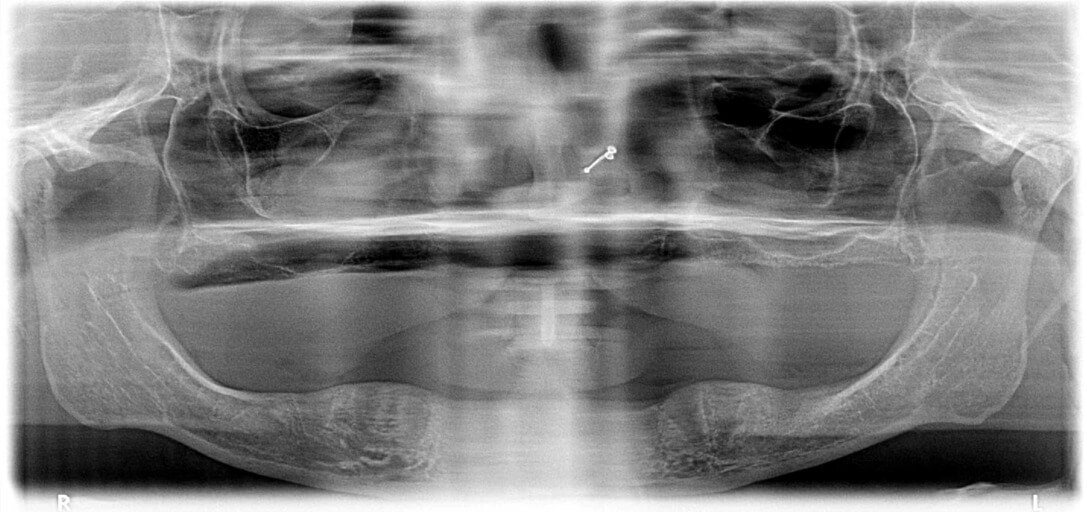

My dentist seen black spots im my jaw wants to to see oral surgeon i asked him how bad he said one of two things iys either nothing or its real bad i dont have insurance to have it checked i do have a copy of my xrays i could send them to u